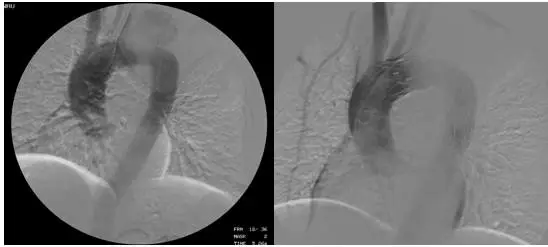

近年來,經(jīng)皮血管內(nèi)支架植入隔絕主動(dòng)脈瘤及主動(dòng)脈夾層破口的微創(chuàng)治療發(fā)展迅速,由于其創(chuàng)傷小、風(fēng)險(xiǎn)低、康復(fù)快,受到很多大醫(yī)院的青睞。

主動(dòng)脈夾層介入治療

惠州三院心血管醫(yī)學(xué)中心自2014年來就逐漸開展胸腹主動(dòng)脈瘤及主動(dòng)脈夾層的支架隔絕術(shù),目前能完全憑借自主力量獨(dú)立完成,是惠州乃至周邊地區(qū)掌握該項(xiàng)技術(shù)為數(shù)不多的醫(yī)院之一。

在肖純副院長指導(dǎo)下,由鐘思干主任、廖火城和劉建平醫(yī)生為核心的大血管團(tuán)隊(duì)經(jīng)過詳細(xì)的論證,最終決定為該患者實(shí)施支架植入的介入治療。歷時(shí)70余分鐘,以廖火城醫(yī)生為核心的大血管團(tuán)隊(duì)以精湛的技術(shù)為患者實(shí)施了胸主動(dòng)脈腔內(nèi)覆膜支架植入術(shù),主動(dòng)脈瘤合并夾層同時(shí)成功隔絕,且無大動(dòng)脈內(nèi)外瘺、截癱、腦梗塞、消化道出血等并發(fā)癥發(fā)生,患者體內(nèi)“定時(shí)炸彈”被成功拆除!